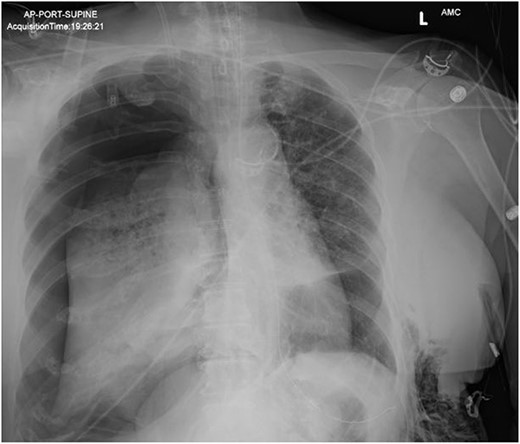

On Hospital Day 2, an interval CXR showed continued resolution of the right-sided pneumothorax but worsening subcutaneous emphysema of the bilateral chest wall and pneumoperitoneum (Fig. 3). Surgical consultation was sought, leading to diagnostic laparoscopy. In the abdomen, emphysematous changes within the gastrohepatic ligament and omental adhesions to the anterior abdominal wall were visualized (Figs 5 and 6). Laparoscopic exploration revealed no diaphragmatic injury or perforated viscera but identified emphysematous changes throughout the preperitoneal space, small and large bowel mesentery, and right paracolic gutter (Figs 7 and 8). Immediate post-op CXR no longer showed evidence of pneumoperitoneum (Fig. 4). The patient was transferred back to the ICU and extubated after three days on Day 5. After the removal of chest tube and transfer to a medical floor on Day 8, the patient developed aspiration pneumonia that was treated with antibiotics. She was discharged on Day 15.

AP upright chest radiograph showing intraabdominal free air, right-sided chest tube in place, and bilateral chest wall subcutaneous emphysema that is worse on the right. Bilateral patchy airspace disease is noted as well.